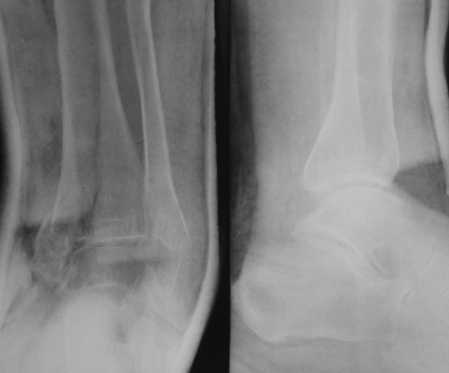

Уважаемые коллеги! Обратилась больная 62-х лет.

Перелом в быту - запнулась о порог в комнате, подвернула стопу.

Рекомендуем первичный артродез.Хотелось-бы услышать мнения по тактике

лечения и способу фиксации.